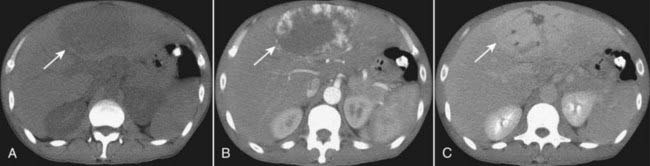

image CT evaluation of liver masses is usually done with a combination of scans obtained before and after intravenous contrast injection. Postcontrast scans are obtained in two phases: one is done quickly (hepatic-arterial phase) and a second is done about a minute later (portal-venous phase), the combination helping to best define and characterize liver masses. This combination of three separate scans done without contrast and then during the arterial phase followed by the venous phase is called a triple-phase scan (Fig. 18-26).

image

Figure 18-26 Triple-phase CT scan of the liver, hepatocellular carcinoma.

Evaluation of liver masses is usually done with a combination of scans including an unenhanced scan (A) and then two postcontrast scans: one obtained quickly (hepatic-arterial phase) (B) and a second (portal-venous phase) slightly delayed (C). The combination of three scans is called a triple-phase scan. This case shows the typical findings of a focal hepatocellular carcinoma. Most are low density (hypodense) or the same density as normal liver (isodense) without contrast (solid white arrow in A), enhance on the arterial phase with IV contrast (hyperdense) (dotted white arrow in B) and then return to hypodense or isodense on the venous phase (dashed white arrow in C).

image Recognizing hepatocellular carcinoma (HCC) on CT and MRI:

There are three patterns of presentation for hepatocellular carcinoma: solitary mass, large multiple nodules, diffuse infiltration throughout a segment, lobe or the entire liver (see Fig. 18-26).

On CT, most HCCs are low density (hypodense) or the same density as normal liver (isodense) without contrast, enhance on the arterial phase with IV contrast (hyperdense) and then return to hypodense or isodense on the venous phase (Fig. 18-32).